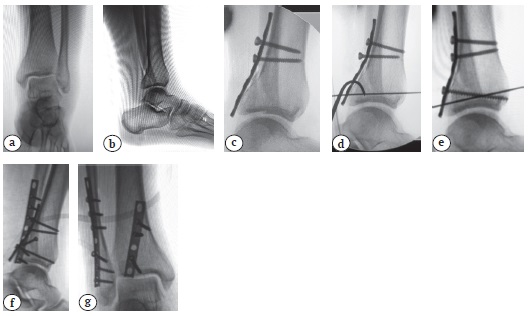

При оскольчатом характере перелома заднего фрагмента ББК Фолькмана для его фиксации применяли пластины (1/3-трубчатые, реконструктивные, Т-образные малые). Такой способ фиксации был выбран у 20 (68,9%) пациентов (рис. 2). В ряде случаев при этом использовали прием последовательного подтягивания пластины к основному метадиафизарному фрагменту кортикальными винтами 3,5 мм сверху вниз, тем самым добиваясь некоторого смещения заднего края ББК книзу и противоскользящего эффекта. Во всех случаях для оценки качества репозиции заднего фрагмента ББК и контроля положения имплантатов применяли интраоперационный ЭОП-контроль в латеральной и прямой проекциях.

Рис. 2. Перелом области голеностопного сустава типа 44-В3 с вовлечением заднего края ББК у пациента 43 лет:a, b — первичные рентгенограммы; с, d, e — этапы репозиции и фиксации заднего фрагмента ББК; f, g — послеоперационные рентгенограммы — фрагмент заднего края ББК фиксирован опорной пластиной и тремя винтами